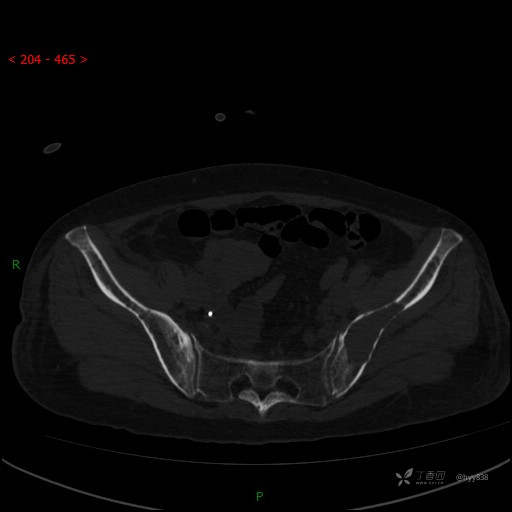

CT平扫

骨窗